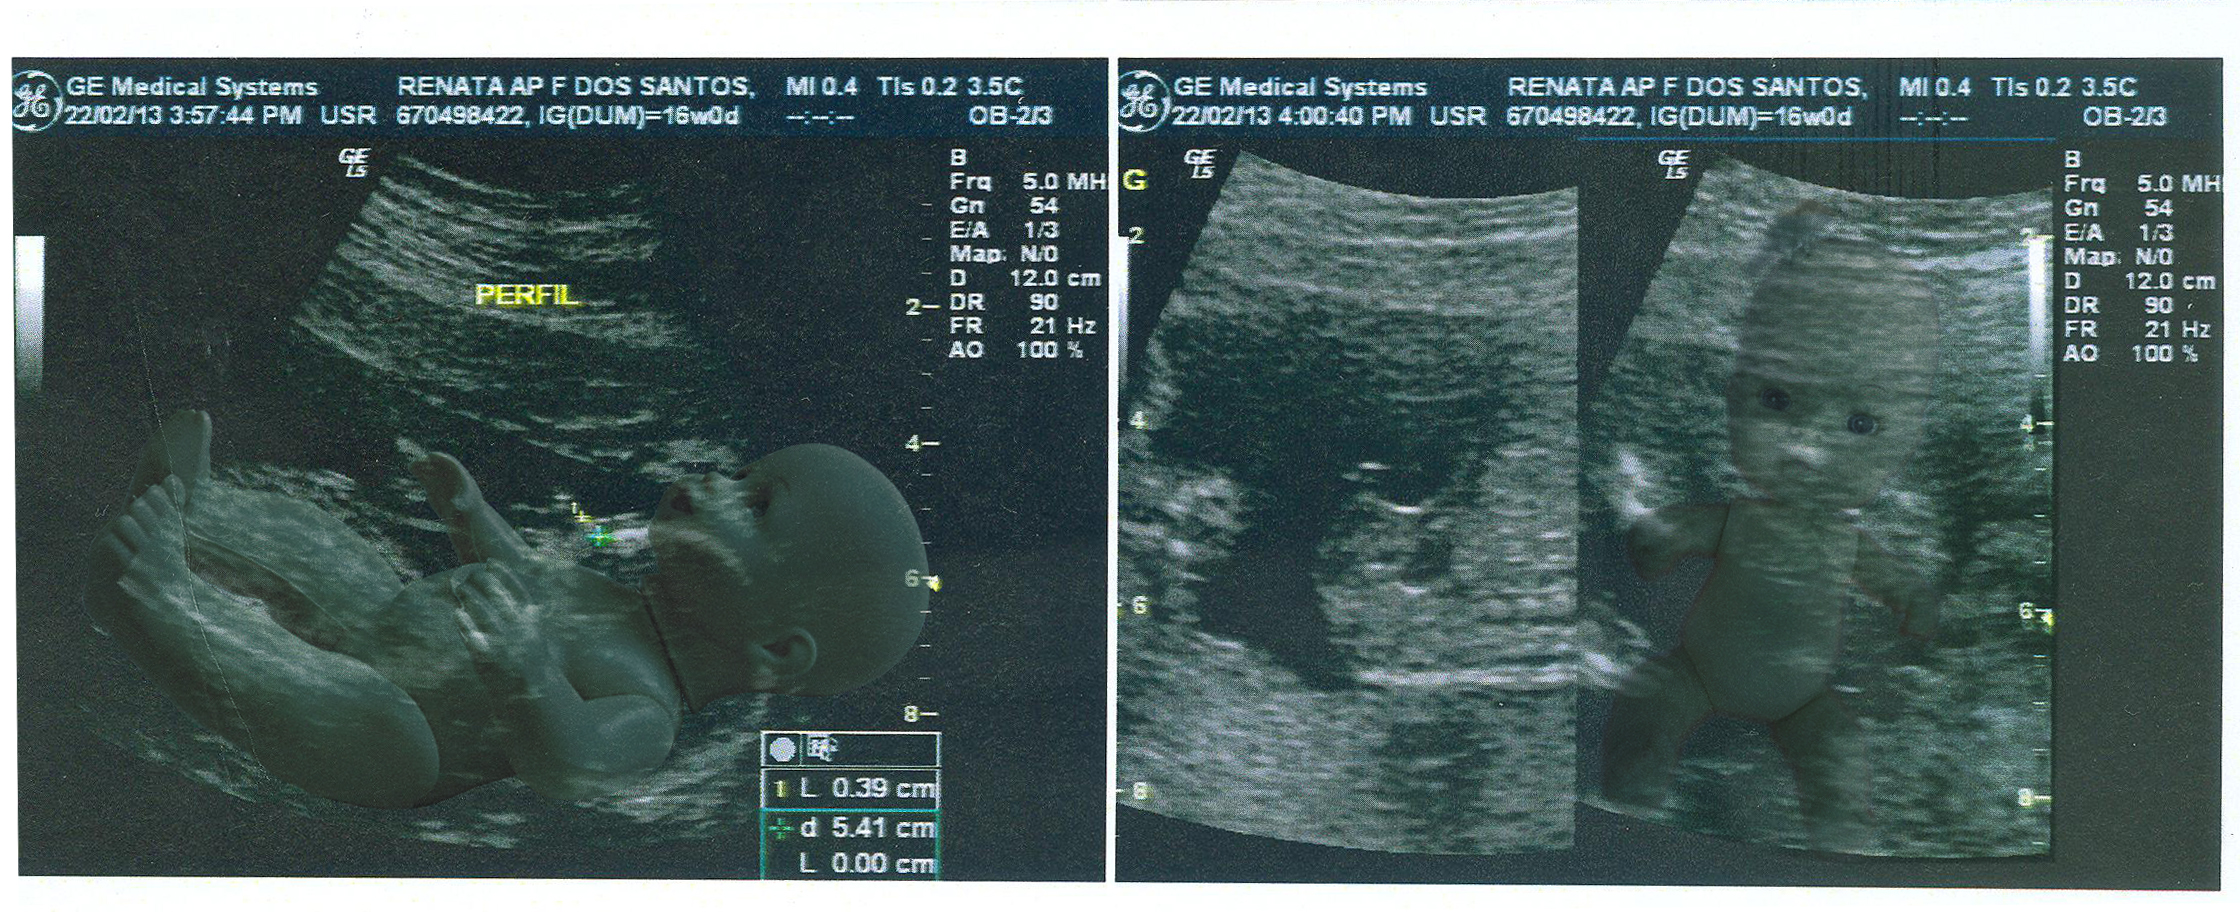

MY BABY (2013)

Manipulated images that also deal with the manipulation of the white imaginary about families and the idea of whitening the race. The marketing of products based on a social construction of white beauty that determines that the products, toys, as well as motherhood, are all desired from the white ideology, including that of giving birth to a white child.